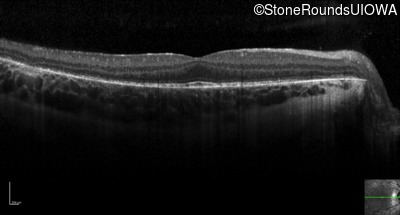

Optical Coherence Tomography - Right - 20/20 -3

Exemplar / OCT Stack

OCT Stack